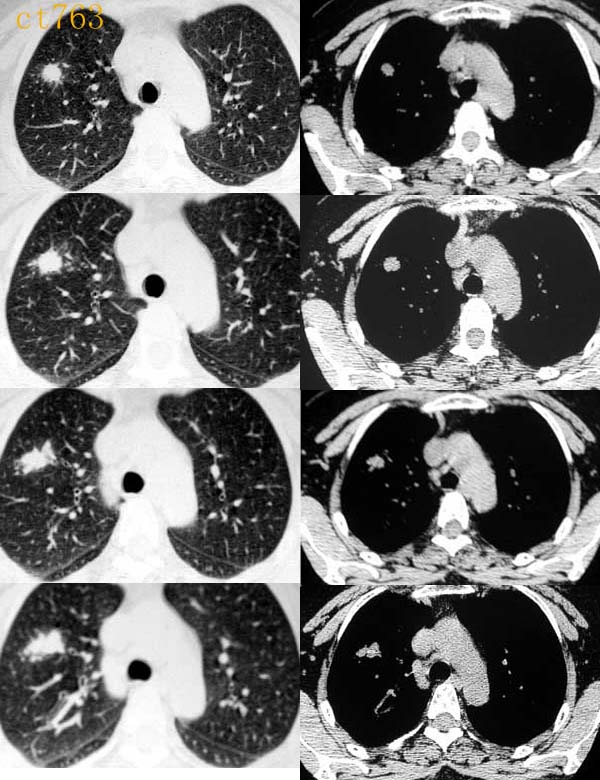

球形肺炎是大叶性肺炎的一种特殊表现[1],以肺的渗出实变为主。它的机理未明,可能是由于抗生素的广泛应用,大叶性或节段性肺炎发展受到限制而形成球形,其形成又与病缘菌的毒性数量及机体的免疫能力有关。病人多有感然症状,某些病人无明显感然症状。病变呈球形或椭圆形,大小不等,病灶密度多均匀,ct值稍低于软组织密度;或中央密度高,边缘密度低,显示晕圈状改变;有时可见空洞[2]。病灶边缘比较规则,也可不规则,有毛刺或呈锯齿状改变,但较模糊。位于肺周区,贴近胸膜,部分病栽表现为两侧缘垂直于胸膜,呈刀切样平直边缘。病灶周围血管纹理增多、增粗、常有局限性胸膜增厚。球形肺炎抗炎两周后,病灶即有缩小,最后能完全吸收。

球形肺炎:病变密度相对较淡,中央密度略高,ct图片上密度较为均匀,增强中央可出现无强化区。病变邻近胸膜反应较为显著,可表现为增厚、粘连(可以比较广泛),病变内可以见到大血管的贯穿,周围及近肺门侧可以见到血管纹理增多、增粗,可有支气管充气征象,两侧可垂直于胸膜或呈方形,边缘可为刀切征,它可以出现毛刺样的类似改变,短期内抗炎治疗有效。